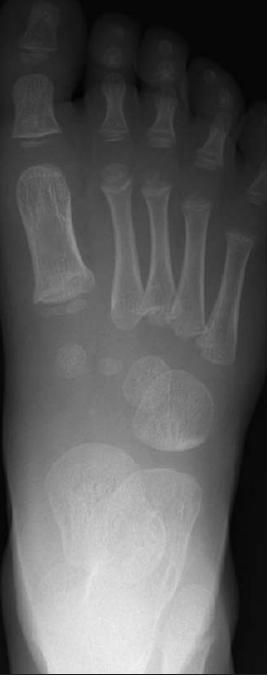

X-ray films of right foot as shown.

The x-ray films show sclerosis of the proximal cuboid bone (arrows), suggestive of cuboid compression fracture.